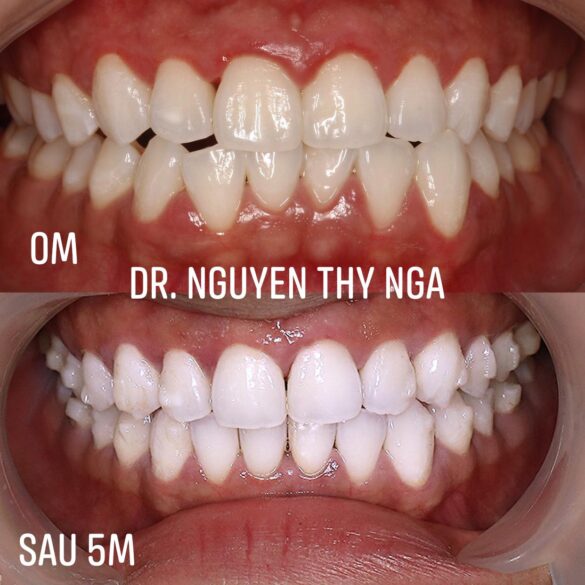

#khớpcắnhở #openbite Dr. Thy Nga Nguyen

𝐓𝐈𝐄̂́𝐍 𝐓𝐑𝐈̀𝐍𝐇 𝐂𝐀 𝐈𝐍𝐕𝐈𝐒𝐀𝐋𝐈𝐆𝐍 ( Đang điều trị )

⭐️ Móm

⭐Sai khớp cắn hạng 3

⭐️Cắn ngược – Cắn đối đầu

⭐️Khe thưa

⭐️R37 xoay 60 độ nghiêng trong về phía lưỡi

👩🏻 Khách hàng mong muốn cải thiện tầng mặt dưới và kiểu mặt lõm. Đóng kín các khe thưa. KH muốn điều trị bằng niềng răng #invisalign và hạn chế các khí cụ khác.

👉 Tổng số khay : 30 ( đã dùng ) + 8 ( đang dùng )

👉Kế hoạch điều trị

💯Chỉ định không nhổ răng

💯Thời gian đeo khay 7 ngày /1 khay

💯Góc nghiêng khuôn mặt, độ cắn chùm và tầng mặt dưới cải thiện rõ rệt sau 5 tháng điều trị

Cám ơn sự hợp tác đeo khay của KH 🥂🥂🥂

TIẾN TRÌNH CHỈNH NHA BẰNG KHAY TRONG SUỐT #invisalign ( ĐANG TINH CHỈNH)

Khách hàng : Nam 27t

Móm – sai khớp cắn hạng 3 | Cắn đối đầu | Cắn ngược đơn lẻ | Cắn hở

Chen chúc trung bình | Lệch đường giữa

Chỉ sau 20 khay vỏn vẹn 5 tháng với trải nghiệm dịch chuyển răng nhẹ nhàng êm ái. Khách hàng đã cảm thấy khá hài lòng ở lượt đầu tiên và thậm chí ko muốn tinh chỉnh.